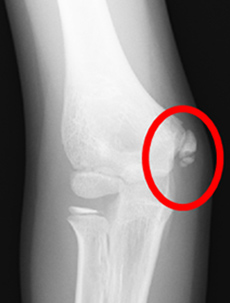

内側型野球肘の画像

肘の内側

正常

(レントゲン)

内側上顆裂離骨折